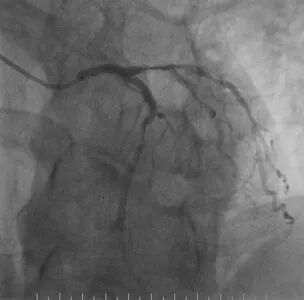

心脑联合造影

-- 右侧颈内起始部中度狭窄,经前交通向左侧代偿

-- 左侧颈内起始部重度狭窄